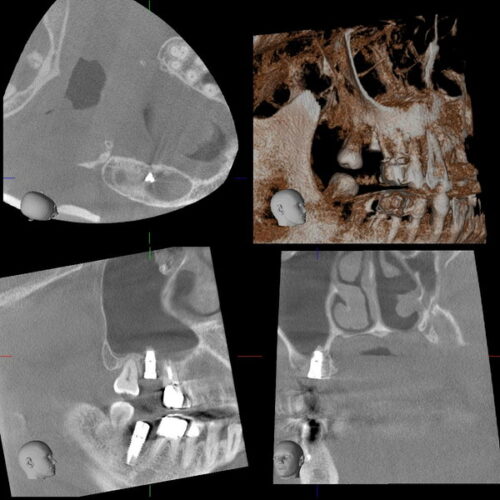

右の上奥歯に1本と右下奥歯に1本の計2本のインプラントオペでした。

上顎の奥歯は、骨の厚みが不足しており、ソケットリフトと呼ばれる骨を足す処置を同時に行いました。

予定通りの位置にしっかりインプラントを処置できたかと思います。